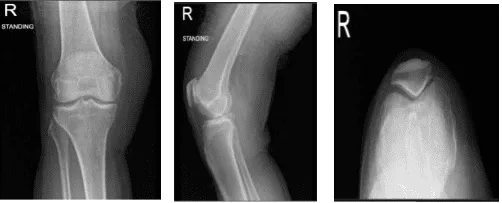

Tras un mes, el paciente fue atendido en la consulta postoperatoria con una radiografía del tobillo izquierdo y también se queja de dolor en la rodilla izquierda, que ha empeorado recientemente. El médico revisó la radiografía, vio la rótula del amanecer y la lateral de pie AP.

El fémur distal, la rótula, la tibia proximal y el peroné proximal presentan márgenes corticales intactos sin fractura aguda. Los espacios de las articulaciones medial, lateral y patelofemoral están bien mantenidos; sin embargo, hay formación leve de osteófitos medial, lateral y patelofemoral.

No hay evidencia radiográfica de derrame articular ni evidencia radiográfica de hinchazón de tejidos blandos. No tiene fracturas, pero sí cambios degenerativos osteoartríticos leves.

Radiografía de rodilla derecha con rótula